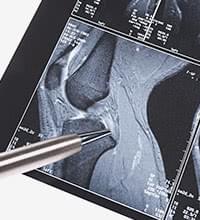

骨だけを描出するレントゲンと違って、MRI検査は骨の内部や軟骨、半月板、靭帯の問題を可視化することができます。また出血や炎症、腫瘍や水腫の有無も確認できます。磁気を利用しているので、他の画像検査のように放射線被爆がない点も特徴のひとつです。

実際の検査画像